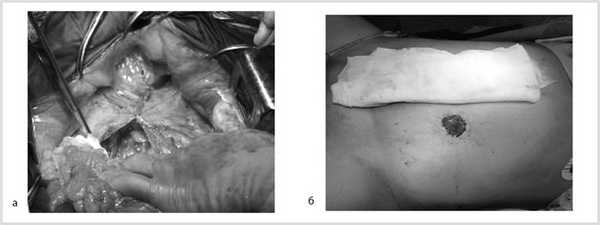

Результаты компьютерной томографии брюшной полости и забрюшинного пространства с внутривенным контрастированием подтвердили наличие неорганного объемного образования левого забрюшинного пространства, интимно прилежащего к левому надпочечнику, краниокаудальный размер которого был равен 241 мм, а максимальный поперечный размер — 143 мм. Структура образования в верхних 2/3 была относительно однородная, в нижней трети — неоднородная за счет наличия двух узлов, без контрастного усиления, что расценено как зона распада. Также визуализировано объемное образование нижнего полюса передней поверхности правой почки размером 25×27 мм с неоднородным контрастным усилением (рис. 1). Рис. 1. Компьютерная томограмма органов брюшной полости (уровень LI—II). 1 — образование нижнего полюса правой почки; 2 — левая почка; 3 — неорганная забрюшинная опухоль.

После тотальной срединной лапаротомии в забрюшинном пространстве слева обнаружена опухоль размером 20×30 см, неотделимая от левой паранефральной клетчатки, располагающаяся от нижнего уровня левой почки и вверх до основания диафрагмы. Брыжейка и левая половина ободочной кишки смещены медиально. Поэтапно тупо и остро в пределах неизмененных тканей (макроскопически опухоль в капсуле) опухоль отделена от задней и боковой стенок живота и прилежащих органов (поджелудочная железа, левый надпочечник). Затем путем маневра Кохера выполнен доступ к правой почке. Произведена мобилизация структур ворот правой почки. Почка выделена из паранефрия. Выявлена опухоль размером 40×30 мм, расположенная на 2/3 экзофитно по переднемедиальной поверхности нижнего полюса правой почки с распространением на ее среднюю часть (рис. 2). Рис. 2. Вид после мобилизации правой почки. 1 — правая почка; 2 — новообразование нижнего полюса правой почки. С учетом данных радиоизотопной сцинтиграфии о снижении функции левой почки решено выполнить органосохраняющую операцию в виде резекции опухоли правой почки. Выполнено временное пережатие сосудов ворот правой почки. Остро опухоль по здоровой ткани иссечена. Раневая поверхность почки прошита непрерывными швами нитью PDS 5/0. Восстановлен почечный кровоток (время ишемии 20 мин). Дефект почки ушит П-образными швами на полипропиленовой сетке (рис. 3). Рис. 3. Вид после резекции опухоли и закрытия дефекта. Почка уложена в свое ложе и укрыта остатками паранефрия.

Заключение прижизненного патолого-анатомического исследования операционного материала: опухоль правой почки — светлоклеточный почечно-клеточный рак, G1, с инвазией в капсулу почки и паранефральную клетчатку, G2 по Furman; паранефральная клетчатка R0, край резекции правой почки R0. Неорганная забрюшинная опухоль — мезенхимальная опухоль забрюшинного пространства с низкой митотической активностью, с очагами некроза опухолевой ткани (рис. 4). Рис. 4. Макропрепарат удаленной гемангиоперицитомы.